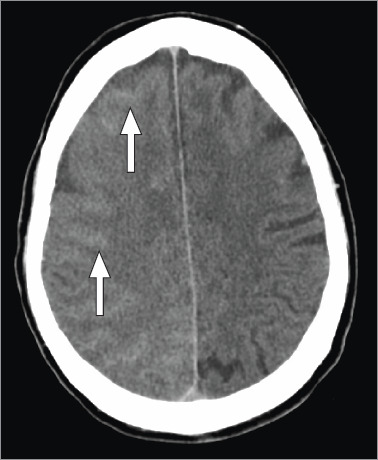

Acute transient contrast-induced neurologic deficit is an uncommon condition triggered by the administration of intra-arterial contrast during angiography. It can present with encephalopathy, cortical blindness, seizures, or focal deficits. This report describes a patient who presented with severe neurologic deficits after percutaneous coronary intervention, with complete symptom resolution within 72 hours.

Abstract Image